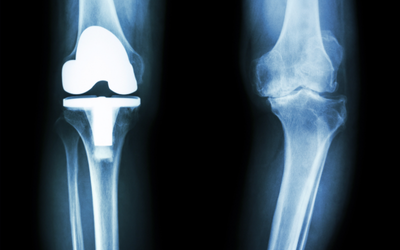

術後にも対応可能

総合病院で約10年間で約4,000件以上のリハビリを担当してきた経験豊富なインストラクターが在籍しています。骨折や靭帯損傷の術後はもちろん、人工関節置換術や脊椎疾患など、幅広い症例に対応可能です。医療現場で培った知識と経験を活かし、術後の不安やお悩みをサポートいたします。「手術したけど、日常生活に困っている」「専門的なサポートを受けたい」という方も、ぜひお気軽にご相談ください。